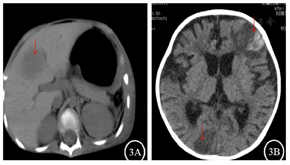

入院后实验室检查:血常规+C反应蛋白(表1),降钙素原0.138 ng/ml。巨细胞病毒(cytomegalovirus,CMV)DNA和EB病毒DNA(EBV-DNA):阴性。真菌D-葡聚糖(G)和曲霉菌半乳甘露聚糖(GM):阴性。血培养:无细菌生长。肝功能:谷丙转氨酶249.9 U/L,谷草转氨酶92.9 U/L,碱性磷酸酶472.3 U/L,γ-谷氨酰转肽酶1135.4 U/L。肾功能、电解质正常。淋巴细胞亚群:T淋巴细胞(CD3+)96%,T8淋巴细胞(CD3+CD8+)92%,T4淋巴细胞(CD3+CD4+)4%,CD4/CD8 0.05,NK细胞(CD16+56+)4%,B细胞(CD19+)0%。胸部CT:肺部团片影(图1A)。积极完善纤维支气管镜检查,肺泡灌洗液革兰染色:检出阴性杆菌、未检出抗酸杆菌。肺泡灌洗液培养阴性、未检出嗜血杆菌。肺泡灌洗液真菌培养基鉴定:未检出真菌。肺泡灌洗液下呼吸道多重细菌核酸检测:肺炎链球菌DNA、金黄色葡萄球菌DNA、耐甲氧西林mecA基因、大肠埃希菌DNA、肺炎克雷伯菌DNA、铜绿假单胞菌DNA、鲍曼不动杆菌DNA、嗜麦芽窄食单胞菌DNA、流感嗜血杆菌DNA、嗜肺军团菌DNA、结核分枝杆菌复合群DNA、肺炎支原体DNA、肺炎衣原体DNA均阴性。肺泡灌洗液宏基因组检测(metagenomics next generation sequencing,mNGS):奴卡菌属;血mNGS:奴卡菌属;PICC管培养:奴卡菌属。胸部CT示肺部片影持续进展,左肺实变伴胸腔积液出现(图1B),右侧第五脚趾呈现黑色(图2A)。影像学CT提示肝脏脓肿(图3A),双侧大脑半球多发团片状异常密度影(图3B)。右侧第五脚趾组织病理培养、骨髓培养、血培养、脑脊液和复查血液mNGS均检出小克银汉霉(图2B~D)。治疗期间血象持续、进行性下降,呈严重骨髓抑制血象(表1)。2021年7月14日行骨穿:骨髓形态增生活跃,粒红系比值形态正常,巨核细胞50个,MRD<0.01%,MLL-AF1P基因阴性,STR示完全供者嵌合状态(姐姐来源细胞占100%)。2021年8月6日复查骨髓形态示增生重度减低,红系两系受抑制,全片未见巨核细胞,MRD<0.01%,MLL-AF1P基因阴性。2021年8月6日行脑脊液检查:脑脊液细胞数为3×106/L,生化正常,体液细胞学未见异常细胞,白血病免疫分型未见异常表型细胞。

2021年8月7日患儿出现右侧手指间断抽搐、嗜睡,完善16排肝脏、头颅CT平扫示肝左叶团状低密度灶、双侧大脑半球多发团片状异常密度影、脑萎缩样改变,提示病情呈进行性进展,家属放弃治疗,随访患儿于当天死亡。

本例患儿为HSCT、CAR-T细胞治疗后,因低热入院。入院后查淋巴细胞亚群示B细胞为0,免疫功能未重建,既往并无真菌感染病史,院外口服氟康唑预防真菌治疗中。入院后虽然予卡泊芬净、伏立康唑积极抗真菌治疗,但肺部仍呈进行性进展,且出现局部组织的真菌感染,组织病理培养为小克银汉霉。经过常规培养和mNGS的检测,骨髓和血、脑脊液均检出小克银汉霉。肝脏CT提示可见脓肿,虽未进行肝脏穿刺活检检查,但患儿基础疾病处于缓解状态,支持脓肿为感染性,结合患儿血液和骨髓均检出小克银汉霉,传播途径应为血流感染播散所致。该明确病原菌后根据诊疗指南,予两性霉素B脂质体应用,由于患儿不能耐受顽固性低钾血症,更换为两性霉素B胆固醇硫酸酯复合物,但该患儿表现不典型,治疗过程检测出奴卡菌属,早期并无明确真菌感染的证据,使毛霉菌感染被掩盖,且感染导致骨髓正常的造血功能被抑制,积极的粒细胞刺激因子升白细胞、输血并未能改善患儿的血象,没有争取足够的时间控制多部位的毛霉菌感染,病情持续恶化,最终死亡。